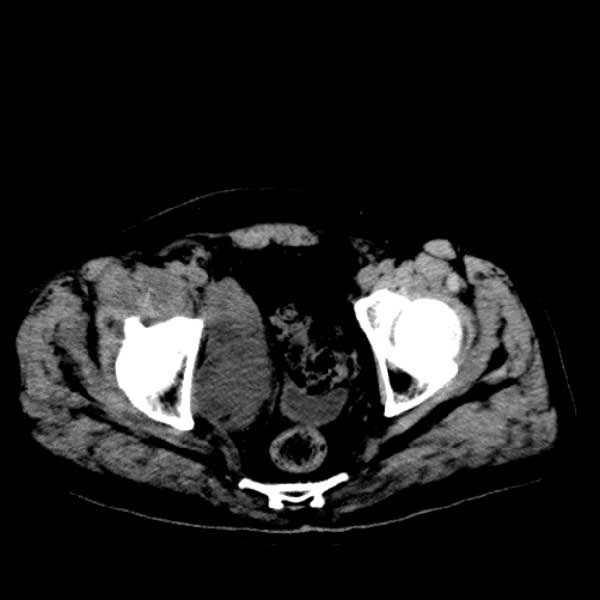

标题: CT13513:男 71 腹部疼痛20余天,近几天高热就诊,骨窗未见异 [打印本页]

标题: CT13513:男 71 腹部疼痛20余天,近几天高热就诊,骨窗未见异

考虑感染性病变可能性大,起源于阑尾?

考虑为化脓性阑尾炎.脓肿形成.及多肌肉累及.

考虑右侧腰大肌脓肿,向右髂窝、右腹股沟流注。

支持化脓性阑尾炎伴右髂窝脓肿、腰大肌腰方肌脓肿形成。

考虑腹腔及盆腔化脓性炎症,累及右侧髋关节及腹股沟区.

首先考虑化脓性阑尾炎伴腰大肌、腰方肌脓肿,不除外回盲部结核。

回盲部癌待排除。

患者肠镜检查考虑结肠癌,病理证实

患者肠镜检查考虑结肠癌,病理证实。肺部ct可见多发结节,考虑转移